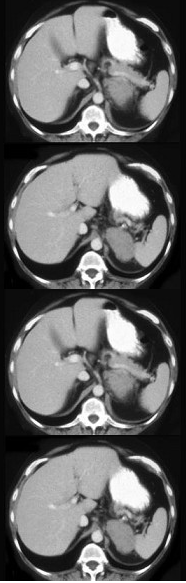

女,47岁,满月脸、向心性肥胖伴高血压1个月,请结合所提供图像,作出诊断( )

A:左肾上腺腺瘤

B:左肾上腺腺癌

C:左肾上腺转移瘤

D:左肾上腺嗜铬细胞瘤

E:左肾上腺增生